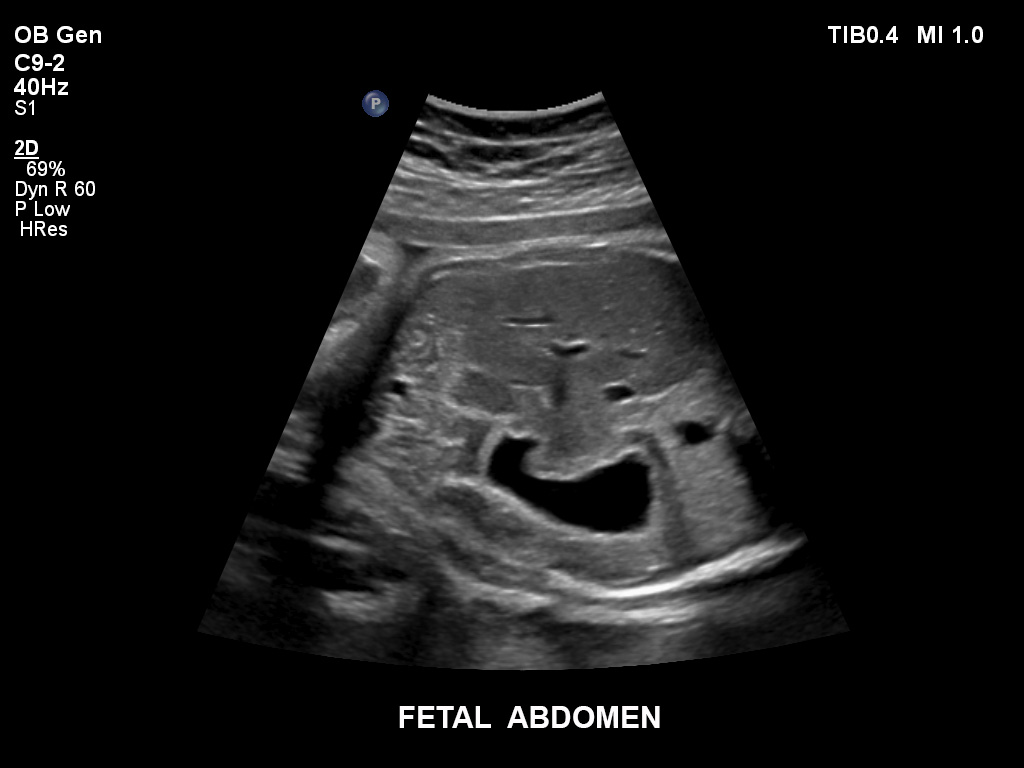

• C9-2 PureWave-Breitband-Convex-Schallkopf für Hochfrequenz-Bildgebung in der Gynäkologie und der Geburtshilfe, insbesondere für die Untersuchung im Hinblick auf mögliche Anomalien im ersten Schwangerschaftstrimester